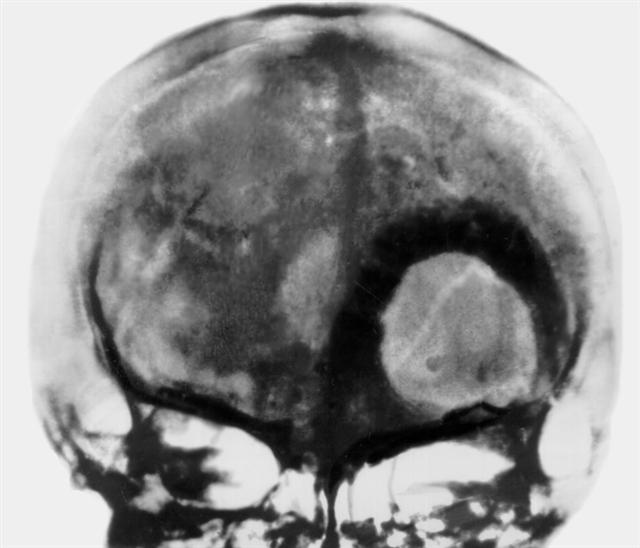

Рис. 11. Переднезадняя рентгенограмма черепа больного с метастазом рака паращитовидной железы в чешую лобной кости слева: имеется круглый очаг деструкции, окруженный широкой зоной остеосклероза.